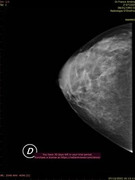

Parenchimi fibroghiandari con componente adiposo nei quali l'esame ecografico integrato da esame mammografico non ha evidenziato aspetti patologici,anche nell'area di maggiore densità parenchimale nel q superiore est di sn. Si consiglia un controllo ecografico fra 6 mesi salvo diversa indicazione clinica.

Queste sono le.immagini della mammografia,e ricordo sempre il motivo oer la quale ho fatto tutti questi accertamenti,presenza di un nodulo o pallina seno sinistro,chr a quanto pare rivelatasi mia conformazione del seno. (Come già da lei ribadito)